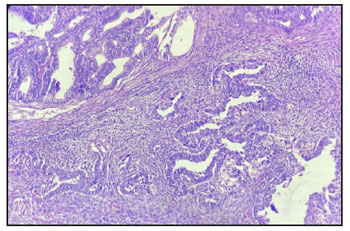

Figure 1: Top right corner shows malignant endometroid

carcinoma and left lower shows clear cell component on H & E

stain.